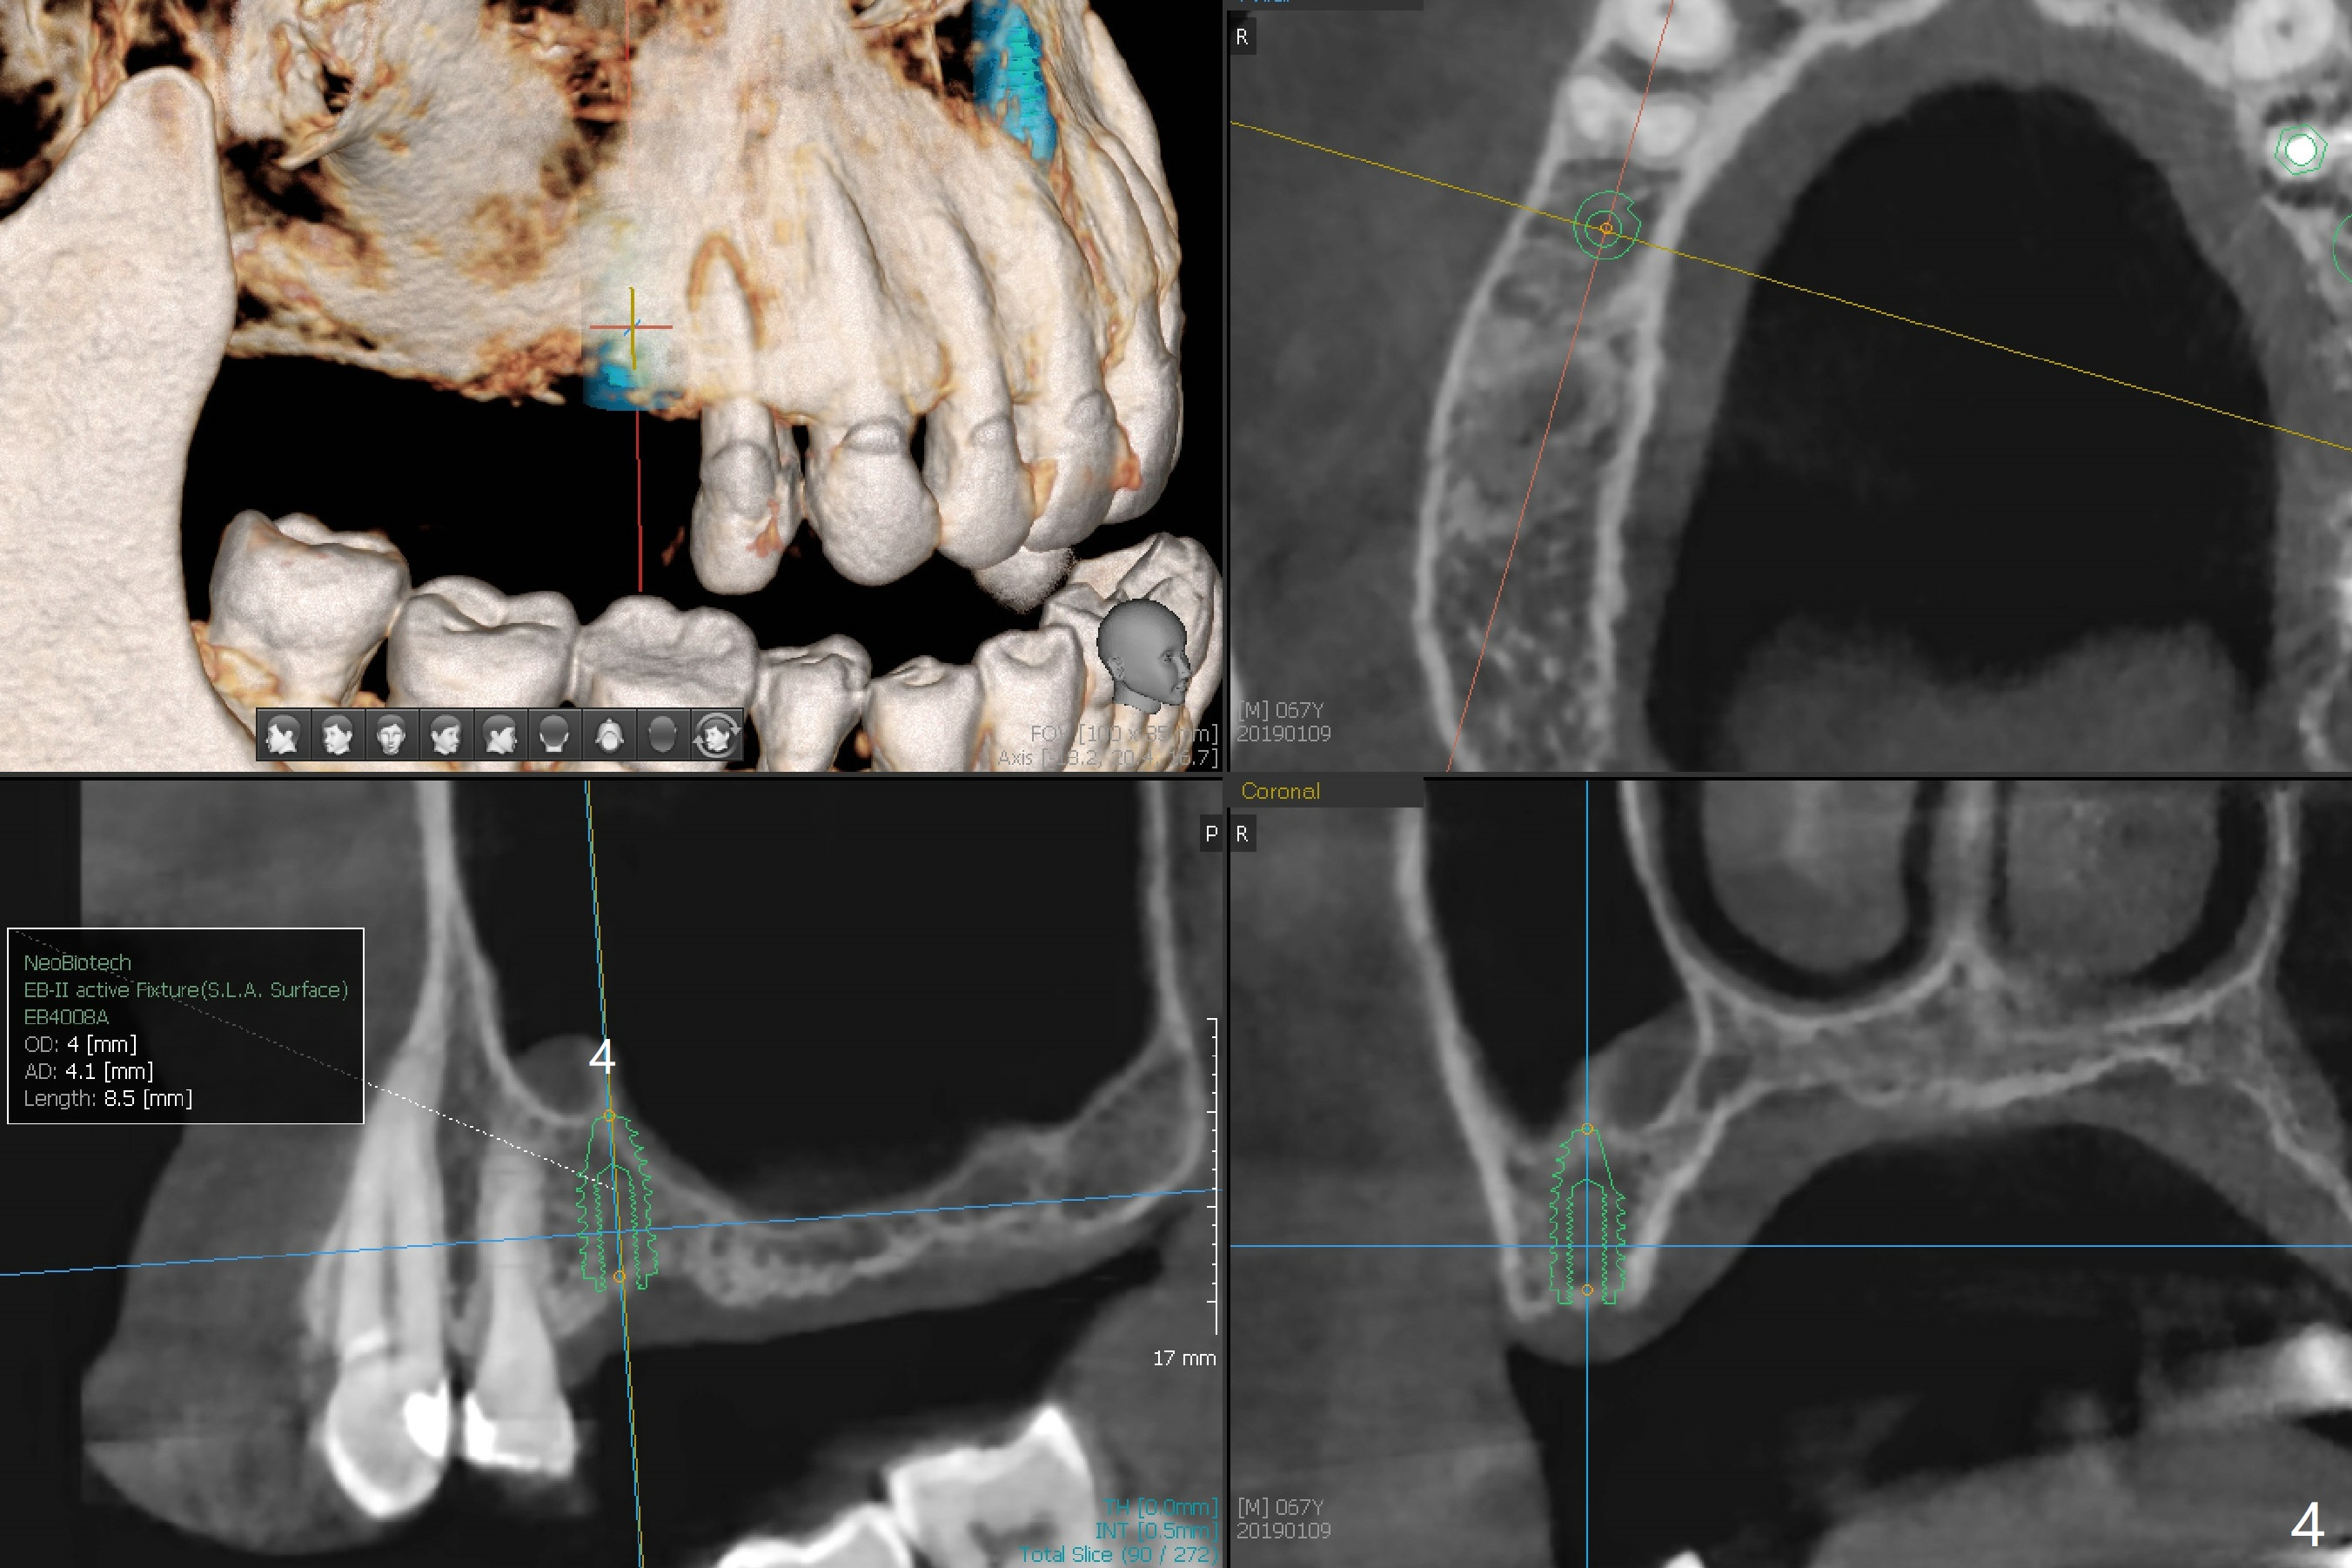

A 63-year-old woman wants to change upper RPD (for #2-4, 13 and 14) to implants because of denture-associated candidiasis. She is afraid of osteoporosis, although the implant at #18 is doing fine almost 3 months post cementation (Fig.1). One way to restore the upper right quadrant is to place 3 short implants (7.3 or 8.5 mm) with guide with simultaneous internal or external sinus lift (Fig.2-4). The tooth #12 appears to have root fracture with periradicular radiolucency (Fig.5); an immediate implant will be placed. While a short implant will be placed at #13, no implant will be placed at #14 because of 1 mm bone (Fig.6). A cantilever FPD will be fabricated in the upper left quadrant. The thick left sinus membrane is a problem as related to a lift?